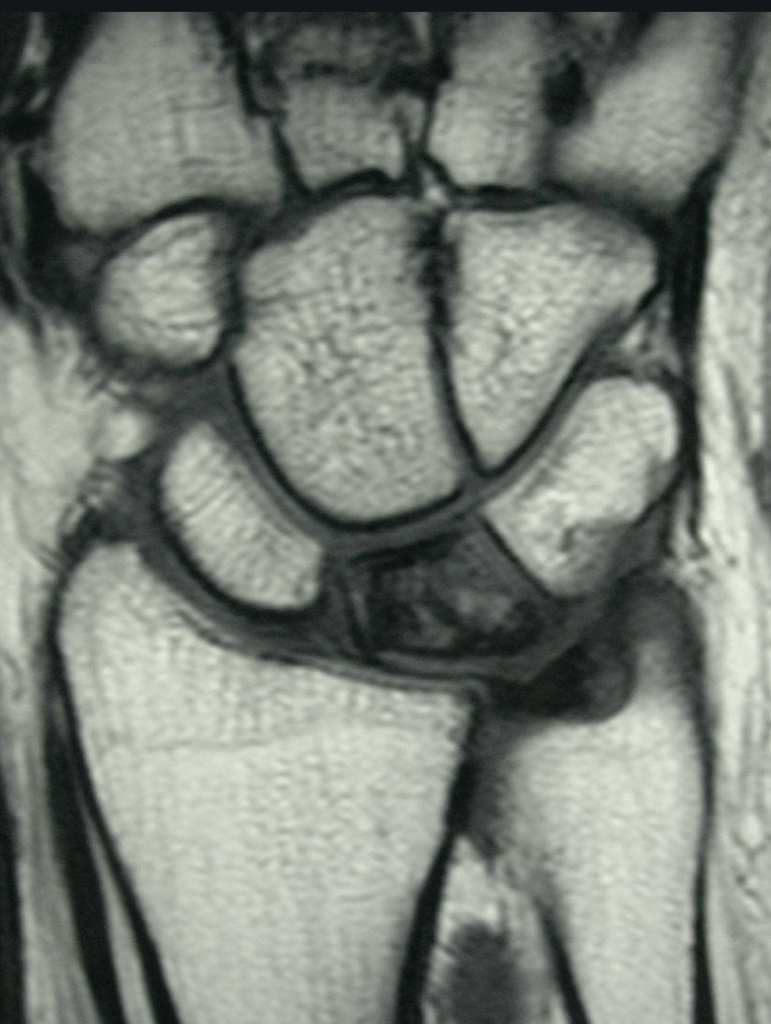

It is actually difficult to determine what will be the natural history of Kienbock’s disease in patients who first present. The condition is sometimes diagnosed very early on, before any xray changes are seen. In other patients the condition presents when the lunate bone fractures or breaks because of bone death.

Kienbock’s disease can be classified according to the changes seen on xrays and scans, and we try to classify the condition in all patients, so that we can give an idea of what is likely to happen. If, for example, a patient presents with stage 2 Kienbock’s, but 6 months later has progressed to stage 3, then we assume that the disease process is active. If no progression of the condition is seen on serial xrays, then we can say that the disease process is static.